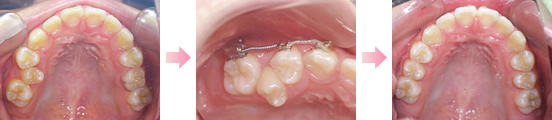

正常な咬み合わせができあがっていくための障害となる要素があった場合、それを取り除き自律的に永久歯列が完成するような口腔環境をつくる考えを基にしております。

可撤性の装置(取り外し可能)や部分的なワイヤー治療にて、比較的負担の少ない装置での治療となります。

治療期間は1年~3年くらい、または小学校6年~中学1年くらいまでが目安になります。

正常な永久歯列を完成することを目的としております。術後の経過観察を行い治療完了となり、その後再び矯正治療の可能性が少ないと言えます。

永久歯の抜歯が必要な症例などは本格矯正の考えの治療と言えます。